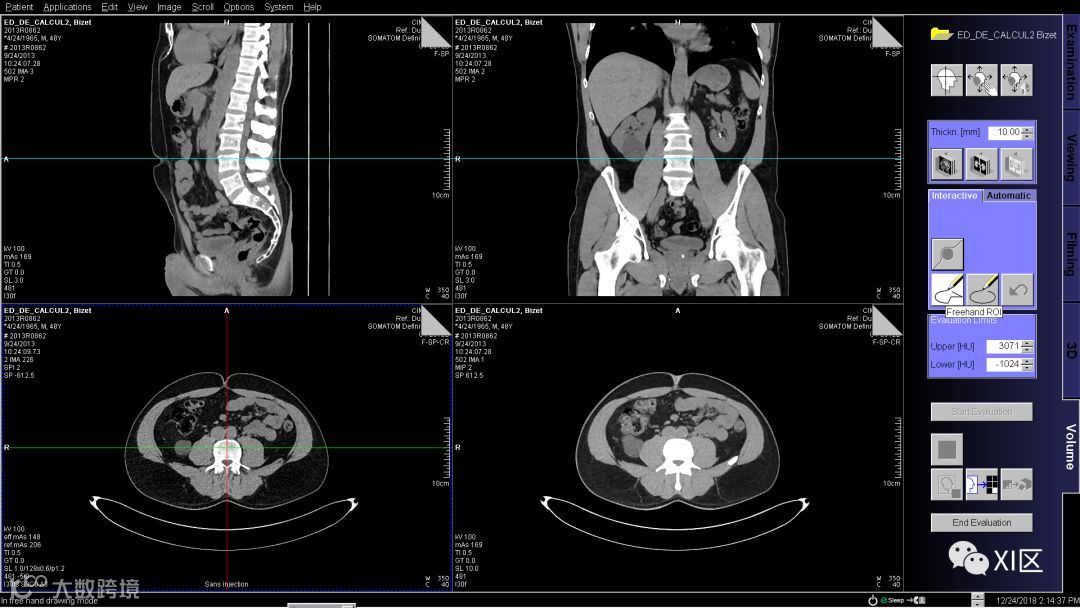

首先,选择10mm层厚的腹部平扫图像导入Volume软件中(在主台或MMWP工作站上),在脐水平的层面使用自由ROI工具将腹壁脂肪勾勒出来,不需要非常精准,只要将需要评估的脂肪都包含进去即可。

勾勒完成后如下图,修改评估阈值为-50到-200HU,然后单击开始评估获得结果。